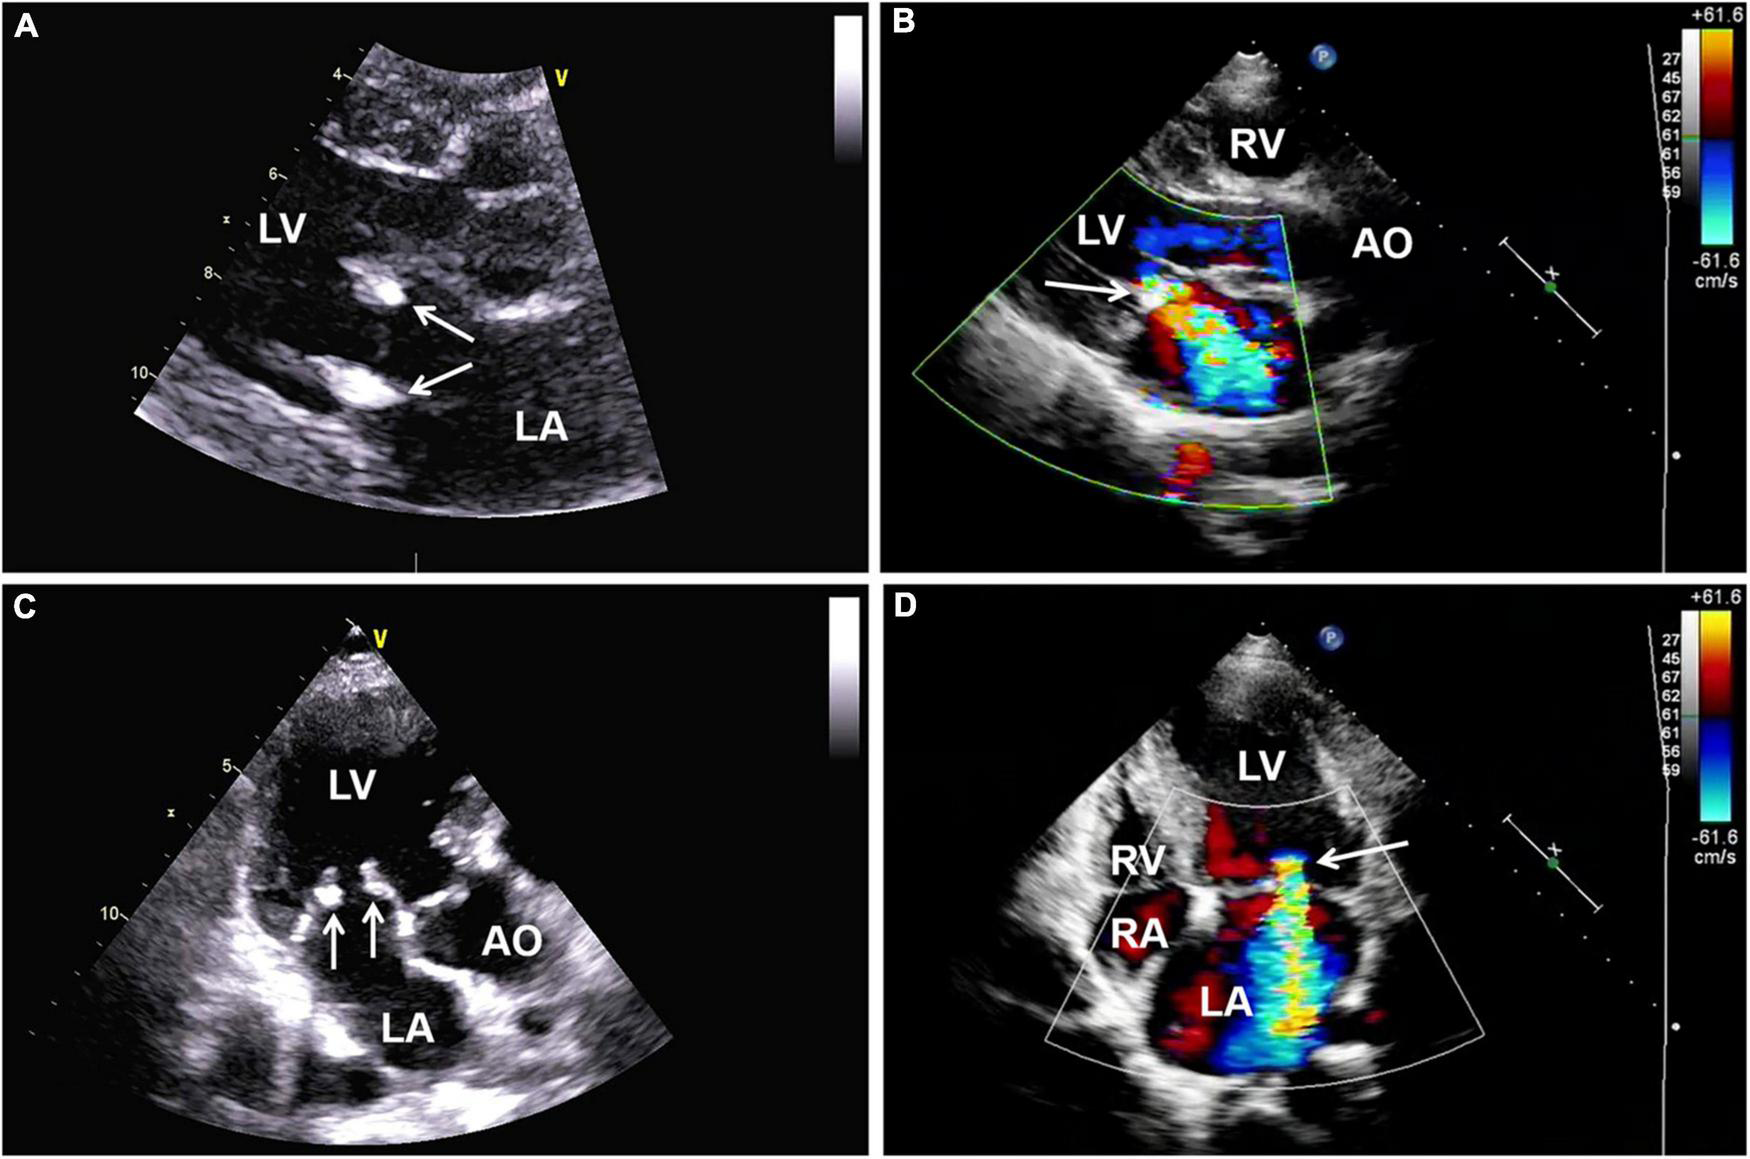

One year later, the patient again sought medical care due to chest tightness and shortness of breath for 2 months. Chest X-ray and chest CT were normal. Additionally, cardiac auscultation revealed a grade 3/6 apical systolic murmur. Follow-up TTE showed thickening and fibrosis of the anterior and posterior mitral valve cusps, mild stenosis (transmitral mean gradient of 3 mmHg and mitral valve area of 2.6 cm2) and moderate to severe regurgitation of the mitral valve (Figure 3) with EROA of 0.40 cm2 and the regurgitant volume of 58 mL. The other valves were normal. The left ventricular function was normal, with a left ventricular ejection fraction (LVEF) of 64%. Repeated blood cultures were again negative. Mitral valve mechanical valve replacement was then performed, which intraoperatively revealed thickening and multiple small nodular vegetations on the mitral valve. No perforation or destruction of the mitral valve was identified. Histopathology demonstrated fibrous tissue hyperplasia with hyaline degeneration and no inflammatory cell infiltration (Figure 4). Postoperatively, oral prednisolone acetate and warfarin were administered with an international normalized ratio (INR) target of 3.0–4.0. During her 17-month follow-up, the patient was clinically stable, the symptoms of cerebral infarction were relieved, and no new infarct was found on the follow-up brain CT. TTE revealed no mitral regurgitation with normal ventricular function.

FIGURE 3

(A,C) Follow-up transthoracic echocardiography (TTE) demonstrating thickening and hyperechoic lesions of mitral valve leaflets (arrows), suggesting valvular fibrosis. (B,D) Color Doppler imaging showing moderate to severe regurgitation of the mitral valve. AO, aorta; LA, left atrium; LV, left ventricle; RA, right atrium; RV, right ventricle; TTE, transthoracic echocardiography.